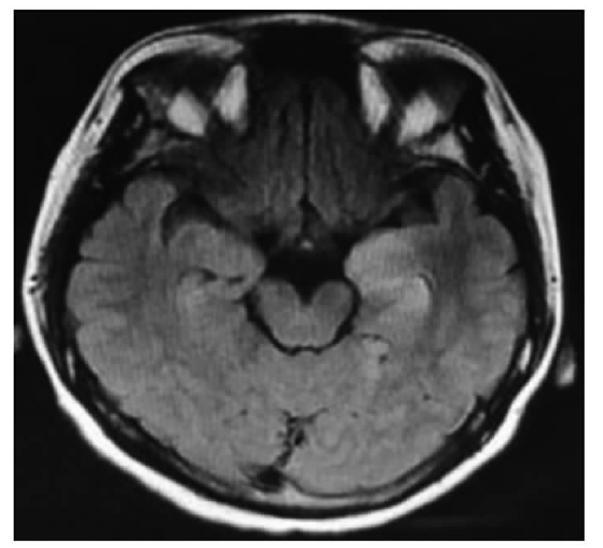

• 皮质基底节变性的影像诊断研究进展

2021, 46(7):818-822. DOI: 10.13406/j.cnki.cyxb.002866

摘要 (70) HTML (289) PDF 1.30 M (184) 评论 (0) 收藏

摘要:皮质基底节变性(corticobasal degeneration,CBD)是一种以不对称的运动症状和大脑皮质功能障碍为主要表现的神经退行性疾病。金标准为病理诊断,临床特征的异质性以及与其他神经退行性疾病在症状和病理方面的重叠性使得诊断难度大。现行诊断标准正确率较低,未将影像学纳入其中。本文主要综述近几十年CBD的影像学进展,包括计算机断层扫描(computed tomography,CT)、磁共振成像(magnetic resonance imaging,MRI)、放射性核素显像等,以及其在疾病鉴别方面的贡献。